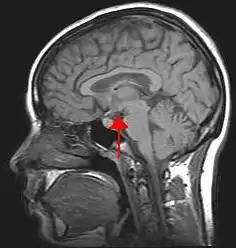

Biological psychology is the scientific study of the biological substrates of behavior and mental states. Seeing all behavior as intertwined with the nervous system, biological psychologists feel it is sensible to study how the brain functions in order to understand behavior. This is the approach taken in behavioral neuroscience, cognitive neuroscience, and neuropsychology. Neuropsychology is the branch of psychology that aims to understand how the structure and function of the brain relate to specific behavioral and psychological processes. Neuropsychology is particularly concerned with the understanding of brain injury in an attempt to work out normal psychological function. Cognitive neuroscientists often use neuroimaging tools, which can help them to observe which areas of the brain are active during a particular task.